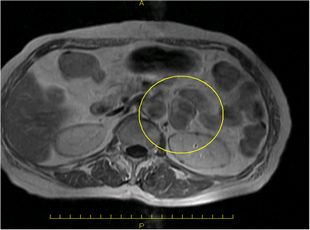

超音波検査、CT検査で副腎腫瘍を認めた場合、血液検査・尿検査などでホルモンを過剰に産生していないかを調べます。

必要に応じてMRI検査や血管造影検査(左右の副腎静脈からホルモンサンプリング)を追加して総合的に診断します。